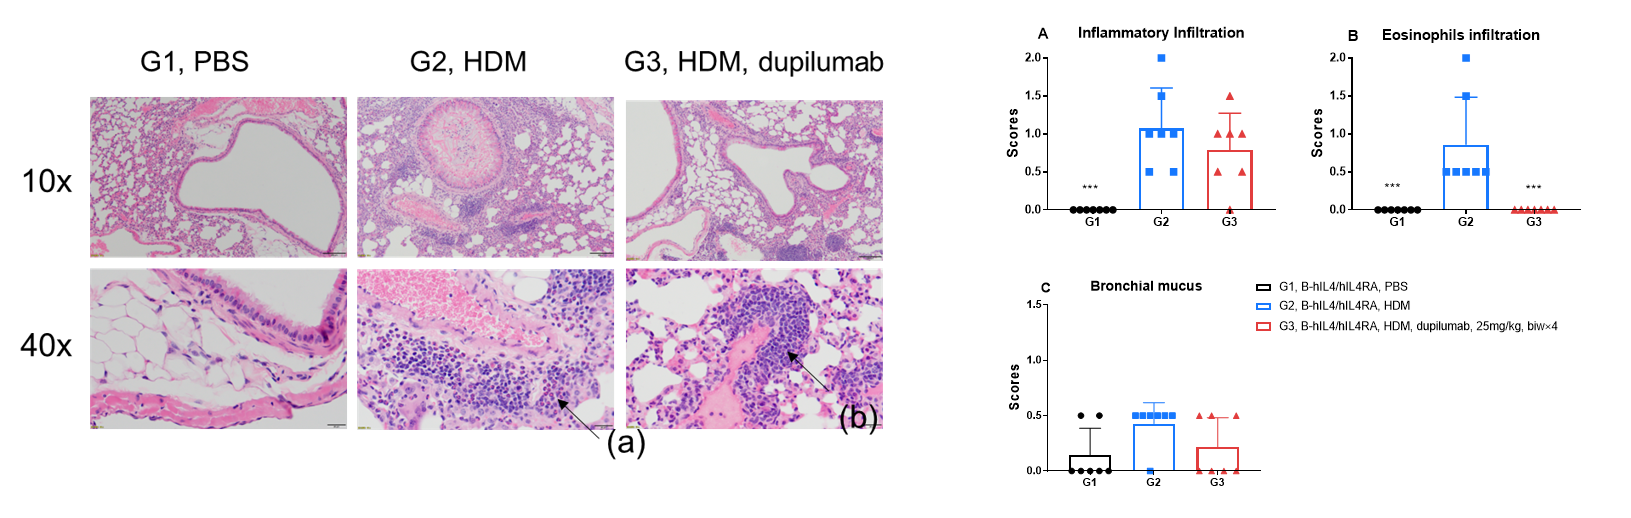

H&E staining in the lungs of asthmatic mice. In contrast to the G1 untreated group, the HDM-treated G2 model group showed asthma-related pathological changes as demonstrated by vascular and peribronchial mixed inflammatory cell infiltration (b) and mucus (a) formation in some bronchi. After administration of dupilumab (in house), the numbers of CD45 + cells and eosinophils were significantly lower compared with the G2 model group.

H&E staining in the lungs of asthmatic mice. In contrast to the G1 untreated group, the HDM-treated G2 model animals showed asthma-related pathological changes as demonstrated by vascular and peribronchial mixed eosinophil cell infiltration (a) and inflammatory cell infiltration (b) in some bronchi. After administration of dupilumab (in house), the numbers of mCD45+ cells and eosinophils were significantly lower compared with the G2 model group. *** P?